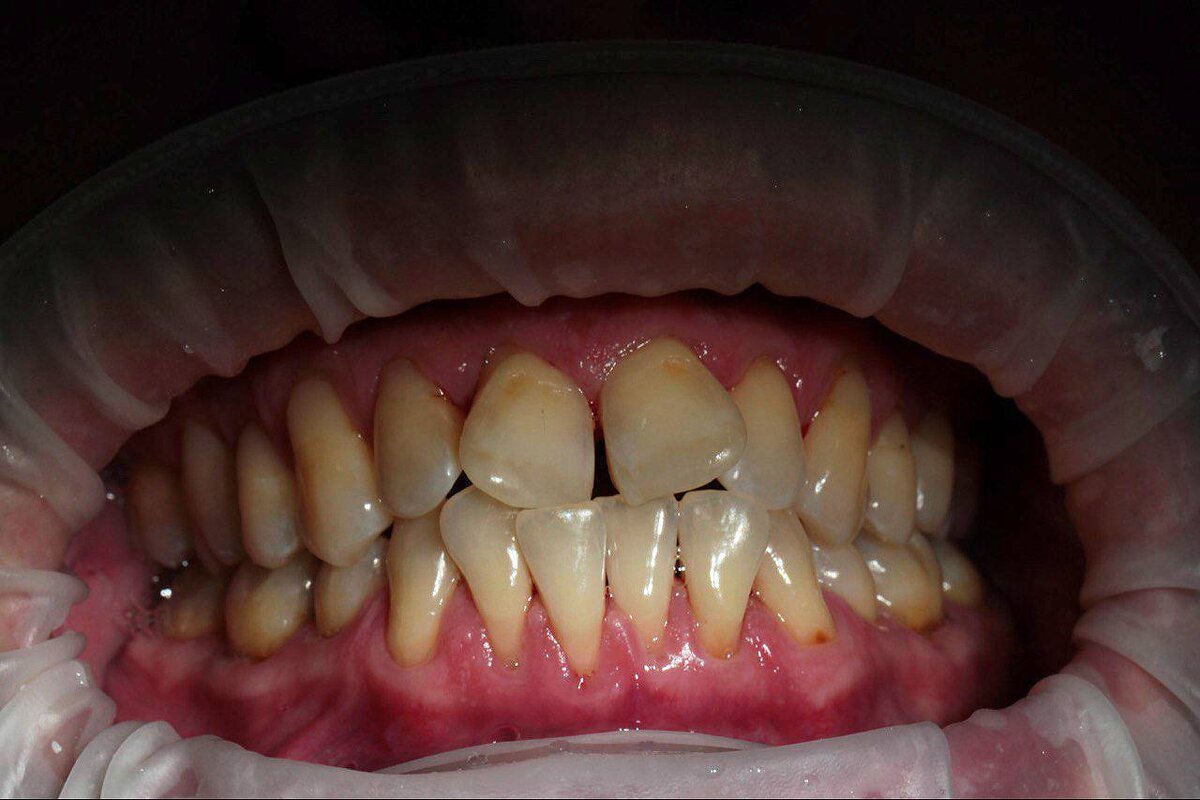

воспринимается, как проблема, а 🫣 остальное как бы и ничего… Что такое остальное: 🔜 заболевания тканей, окружающих зуб (гингивит, пародонтит, пародонтоз) 🔜 некариозные поражения зубов, возникшие до прорезывания (флюороз, гипоплазия эмали, «тетрациклиновые» зубы)и после прорезывания (клиновидные дефекты, патологическая стираемость, эрозия эмали, гиперестезия) 🔜 заболевания слизистой оболочки полости рта 🔜 проблемы с ВНЧС 🔜 аномалии прикуса и положения зубов 🔜 онкологические заболевания 🔜 проявления системных заболеваний в полости рта Давайте так: здоровье полости рта - это не только отсутствие «дырок»!!!! #стоматолог #Москва

🔜 заболевания тканей, окружающих зуб (гингивит, пародонтит, пародонтоз)

🔜 некариозные поражения зубов, возникшие до прорезывания (флюороз, гипоплазия эмали, «тетрациклиновые» зубы)и после прорезывания (клиновидные дефекты, патологическая стираемость, эрозия эмали, гиперестезия)

🔜 аномалии прикуса и положения зубов